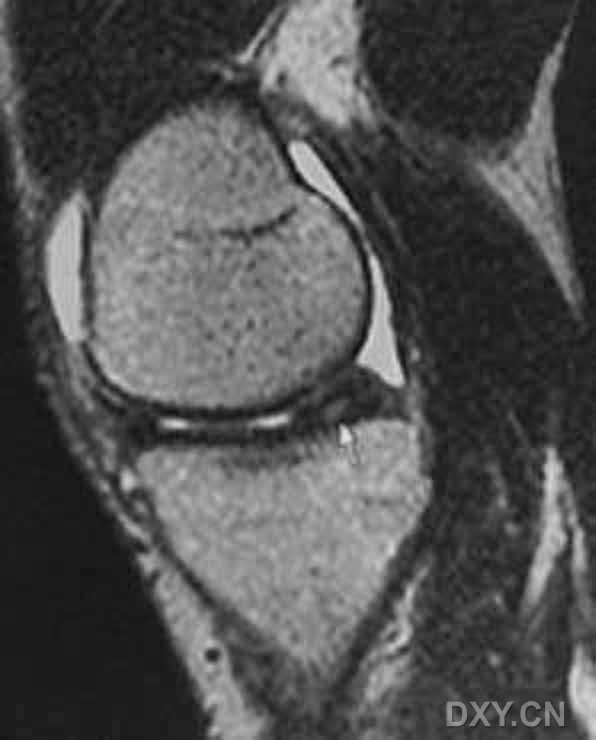

| III级 内侧半月板后角内见线形高信号达到半月板的关节面下缘